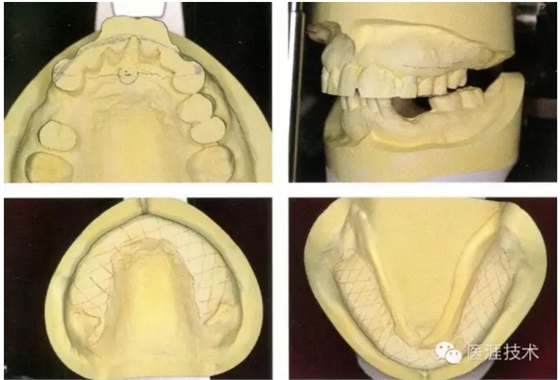

05,根據(jù)咬合平面板,設(shè)計(jì)理想的上頜切牙的位置

06,正確的上頜切牙乳頭的位置應(yīng)該在,上頜前牙切端離開(kāi)7-8mm處,因此需要對(duì)牙槽脊進(jìn)行修整。同時(shí)考慮到正中矢狀面的正中對(duì)稱,咬合面同高等原則對(duì)模型整體進(jìn)行修整。

07,使用咬合平面板再次確認(rèn)修整接受后的模型,模型修整過(guò)程中盡量以咬頜架為參考,避免過(guò)多的削除石膏。使用咬合平面板的測(cè)量起到非常關(guān)鍵的作用。(下頜的確認(rèn)使用咬合面曲面板,預(yù)估削除量)。